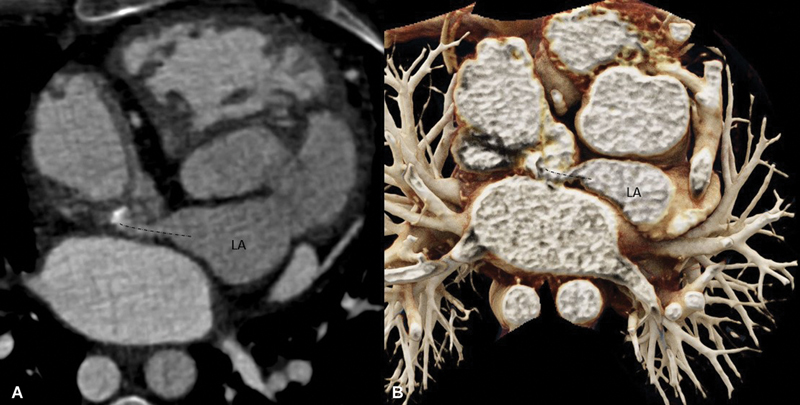

心房转换手术适用于大动脉转位患者。这种手术的并发症之一是造成挡板阻塞。我们描述了一个此类病例的计算机断层扫描结果,在该病例中,一名曾接受过大动脉转位房内修复手术的成人除了肺静脉引流受阻外,还延迟出现了复发性芥末挡板阻塞。

Atrial switch surgery is performed in patients with transposition of the great arteries. One of the complications of this surgery is obstruction of the baffle created. We describe the computed tomography findings of one such case where there was delayed presentation of recurrent Mustard baffle obstruction in addition to pulmonary venous drainage obstruction in an adult previously operated on for intra-atrial repair of transposition of the great arteries.